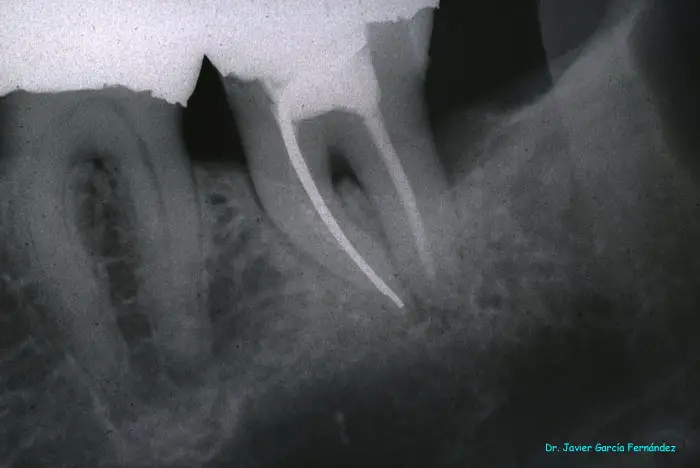

Atlas of Surgical Techniques in Periodontics. Chapter I. Diagnostic of Peridontal Diseases. Classification. Atlas de Técnicas Quirúrgicas en Periodoncia. Cap. I. Exploración y Diagnóstico. Atlas de Técnicas Quirúrgicas en Periodoncia

image157